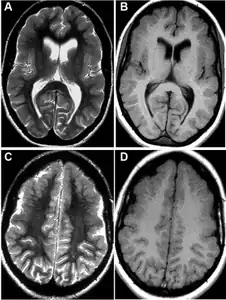

MRI-a,b,c,d)Developmental abnormalities/polymicrogyria in the frontal opercular cortex bilaterally

Magnetic resonance imaging

MRI is one of the best techniques that can detect the lesions in the brain of the FCMS that some of the times are missed by just using a Computer-Tomography Scan. Also, this type of imaging can reveal right frontal lobes contusions encompassing the anterior operculum, the premotor area, and the association area.[10]